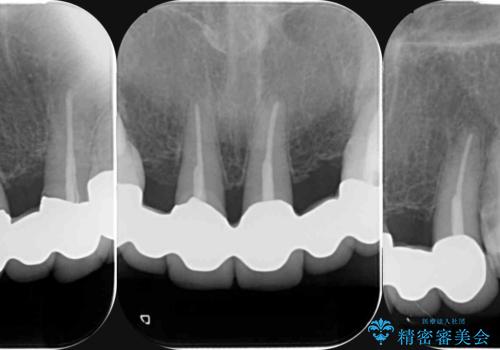

- 20年前に入れたブリッジの見た目の改善を求めて来院されました。

丁寧に現在装着されているブリッジを除去後、精度の高いジルコニアブリッジで審美性の改善を計画します。

前歯に限らず拡大鏡を用いた精密な形成・シリコンを用いた精度の高い印象を徹底することで治療全体の質を高め、審美性だけでなく長期的な予後を期待することができます。